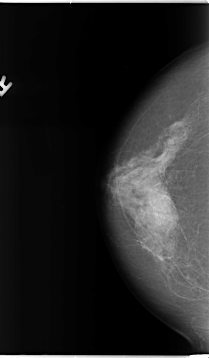

B_3093_1.LEFT_MLO

LEFT_CC LINES 4656 PIXELS_PER_LINE 3016 BITS_PER_PIXEL 12 RESOLUTION 50 OVERLAY

FILE: B_3093_1.LEFT_CC.OVERLAY

TOTAL_ABNORMALITIES 1

ABNORMALITY 1

LESION_TYPE MASS SHAPE ARCHITECTURAL_DISTORTION MARGINS ILL_DEFINED

ASSESSMENT 4

SUBTLETY 3

PATHOLOGY BENIGN

TOTAL_OUTLINES 1

BOUNDARY